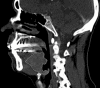

Figure 2

Figure 2. Computed tomography of the neck with contrast revealed a large infiltrative lingual mass suspicious for carcinoma measuring approximately 4.1 x 3.4 x 3.6 cm (dotted line). The mass can be seen involving the lingual surface of the epiglottis and inseparable from portions of the hyoid bone.